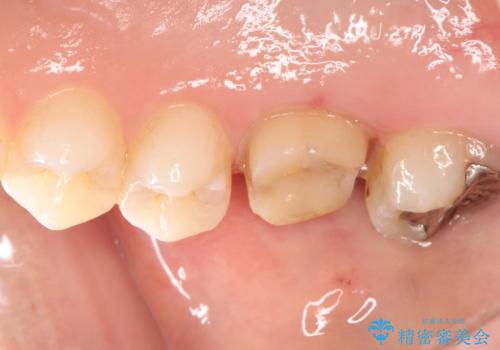

根の神経が細菌に感染するとこのように、膿の出口ができることがあります。

その場合は、根の中の治療(根管治療)が必要になります。

根管治療の注意事項(リスク・副作用など)

- 根管治療により類似の全ての症例の問題が解決するわけではなく、症例はあくまでも一例です

- 根管治療により痛みや腫れがひかない事や、術後に痛みや腫れが生じる事、治療によるファイル破折やパーフォレーションなどの偶発症、術後の歯根破折を生じる可能性もあります